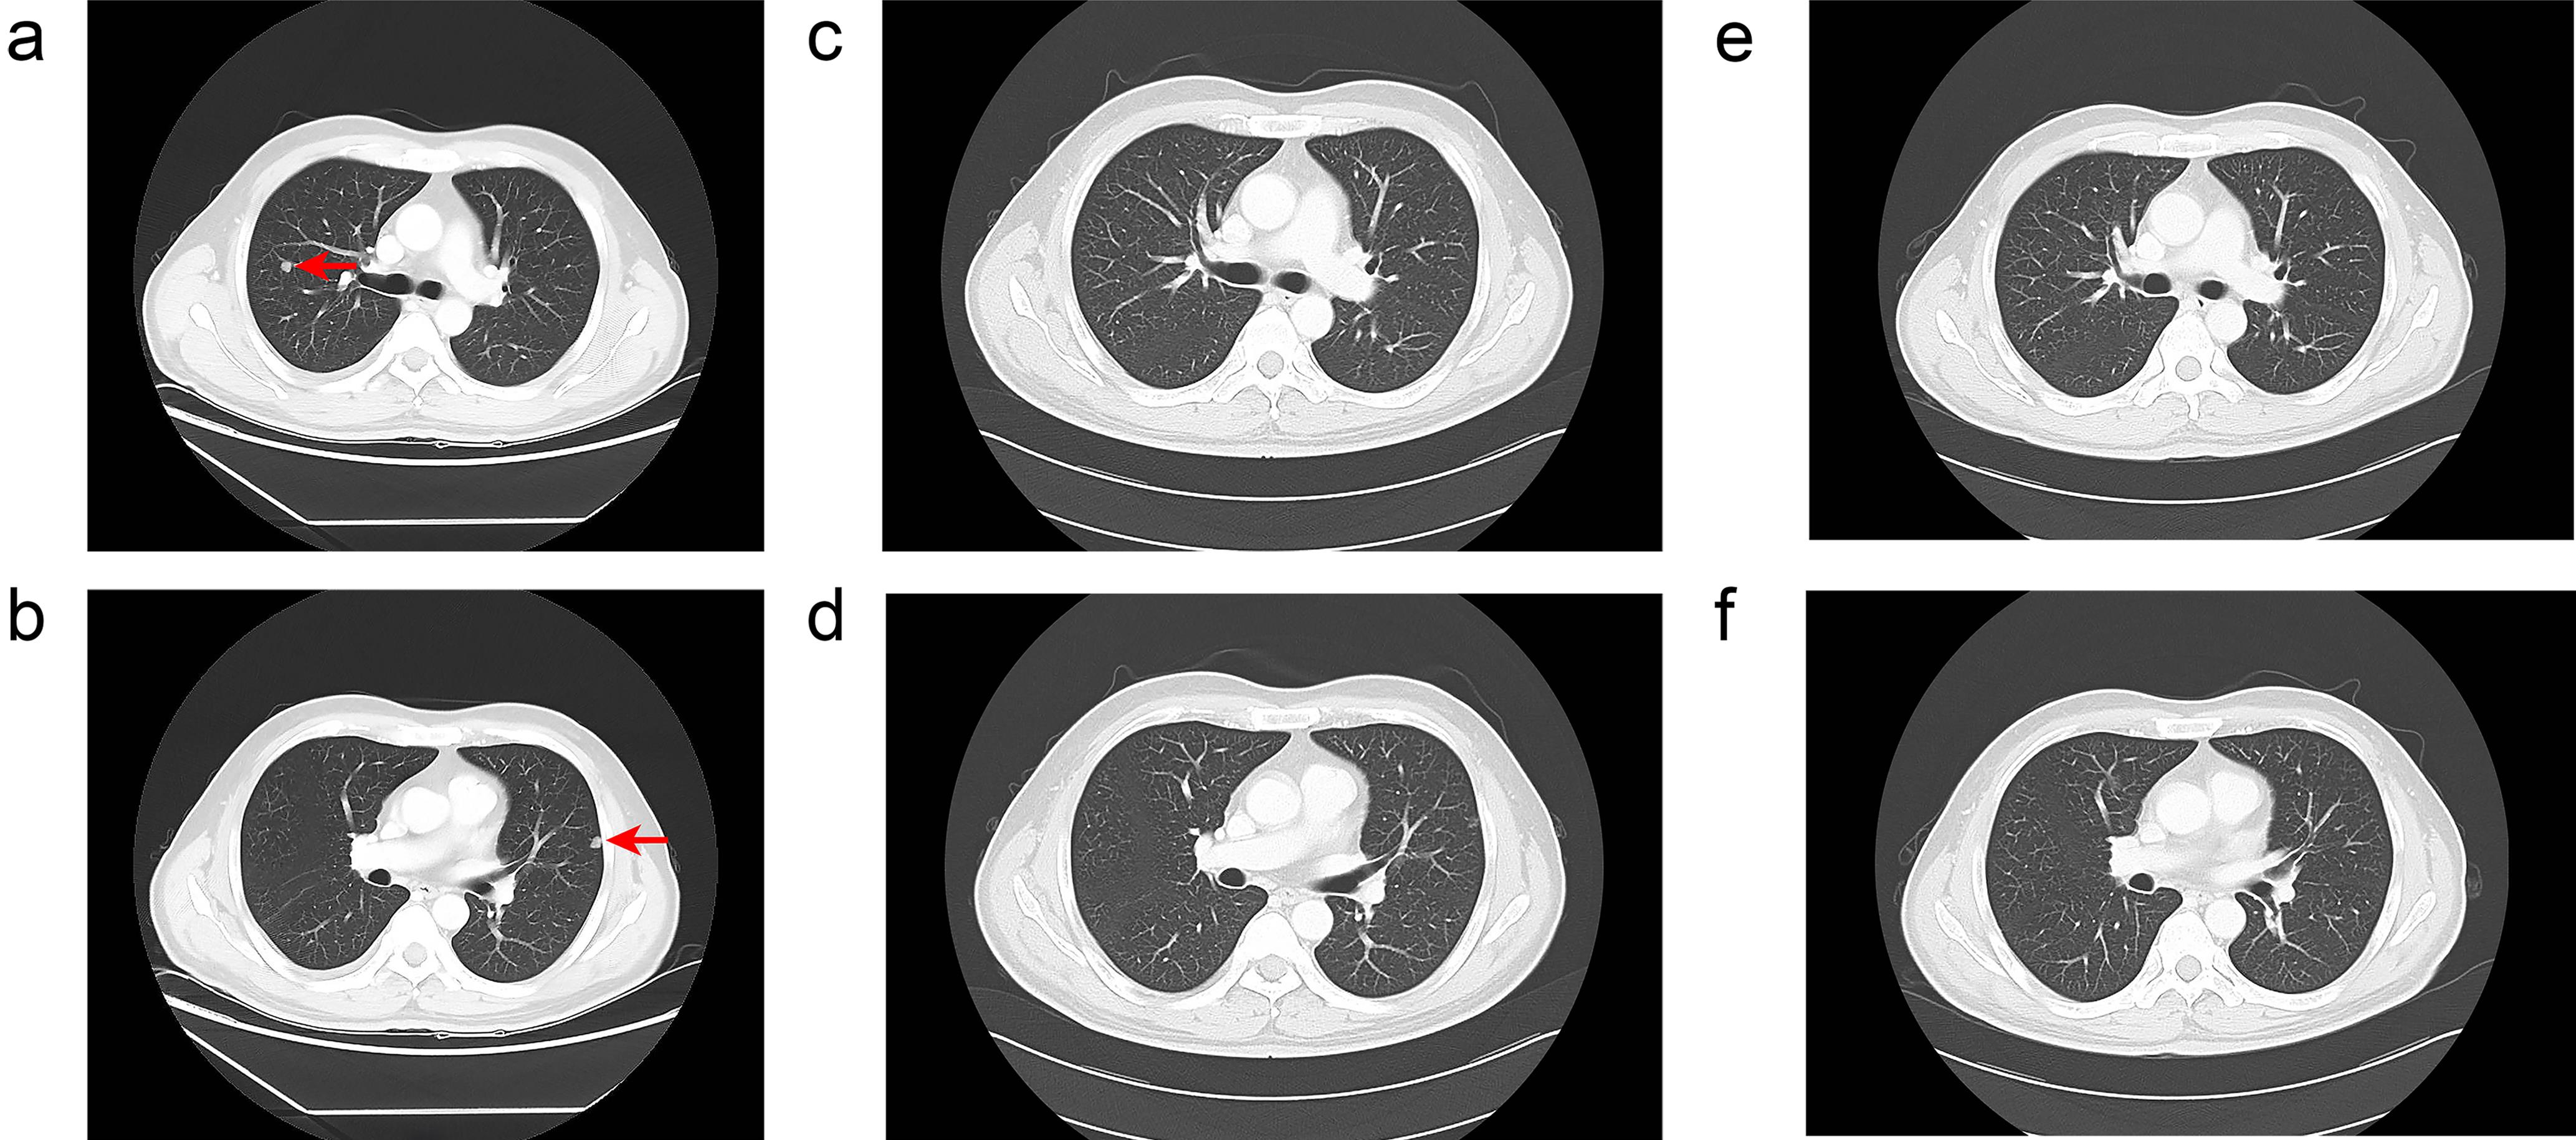

A 46-year-old Chinese male was admitted to our hospital with severe abdominal pain that had persisted for one day. The patient had a chronic hepatitis B viral infection and had not received any treatment over the past two decades. Physical examination showed no abnormalities. The patient’s Eastern Cooperative Oncology Group performance status score was 0. Serum alpha-fetoprotein level exceeded 2,000 ng/mL, and the level of protein induced by vitamin K absence or antagonist-II was 10,730 ng/mL. Enhanced computed tomography revealed two large nodular tumors located in the upper and lower segments of the right posterior lobe of the liver. The largest tumor measured 9.3 × 5.2 × 8.1 cm. Part of the tumor protruded beyond the liver surface and extended into the left lower quadrant. Hypodense areas within the tumor suggested liquefaction necrosis due to rupture and hemorrhage (Fig. 1a and b). The intrahepatic tumor burden exceeded 60% of the total liver volume. Multiple bilateral pulmonary metastases were also detected, with the largest lesion measuring 0.8 × 0.7 × 0.8 cm (Fig. 2a and b).

Computed tomography images of the lung showing pulmonary metastases at different time points.

Fig. 2  Computed tomography images of the lung showing pulmonary metastases at different time points.

(a, b) November 2, 2023. The red arrows indicate metastatic tumors. (c, d) January 18, 2024. No pulmonary metastases were detected. (e, f) May 10, 2024. No pulmonary metastases were detected.

After three months of treatment, enhanced computed tomography revealed no signs of tumor progression. According to RECIST 1.1,7 the intrahepatic tumors exhibited a partial response (Fig. 1e and f), and the bilateral lung metastases showed a complete response (Fig. 2c and d). After seven months, the patient returned for follow-up, and complete response status was maintained (Figs. 1g and h, 2e and f). The levels of alpha fetoprotein and protein induced by vitamin K absence or antagonist-II decreased to normal levels (Fig. 3a and b, Table S1). In total, the patient received nine cycles of tislelizumab and seven months of lenvatinib. The patient continues to undergo regular monthly blood counts and liver function tests to monitor for adverse events. No significant immune-related adverse effects, including liver dysfunction, hypertension, or proteinuria, were observed during treatment. Follow-up is ongoing (Fig. 4).